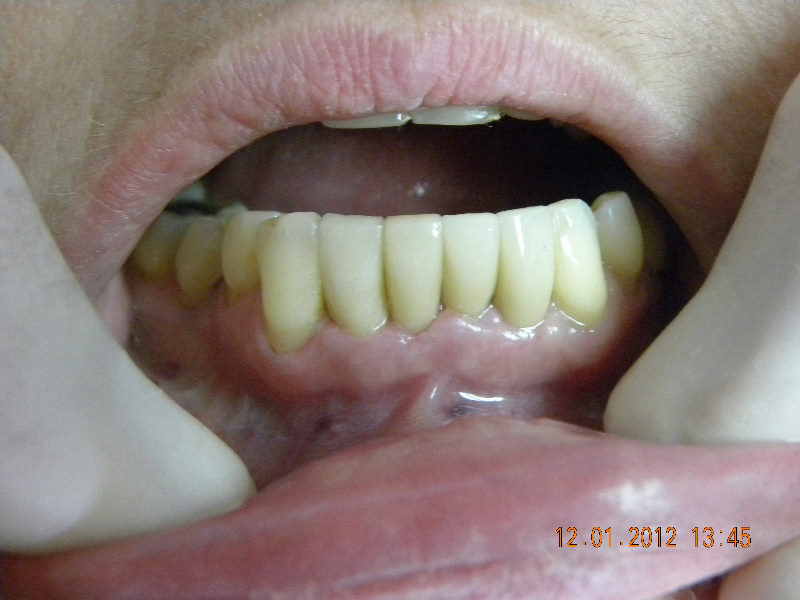

Colocación de implante y carillas libres de metal

Envíado por Grupo Dental de El Salvador